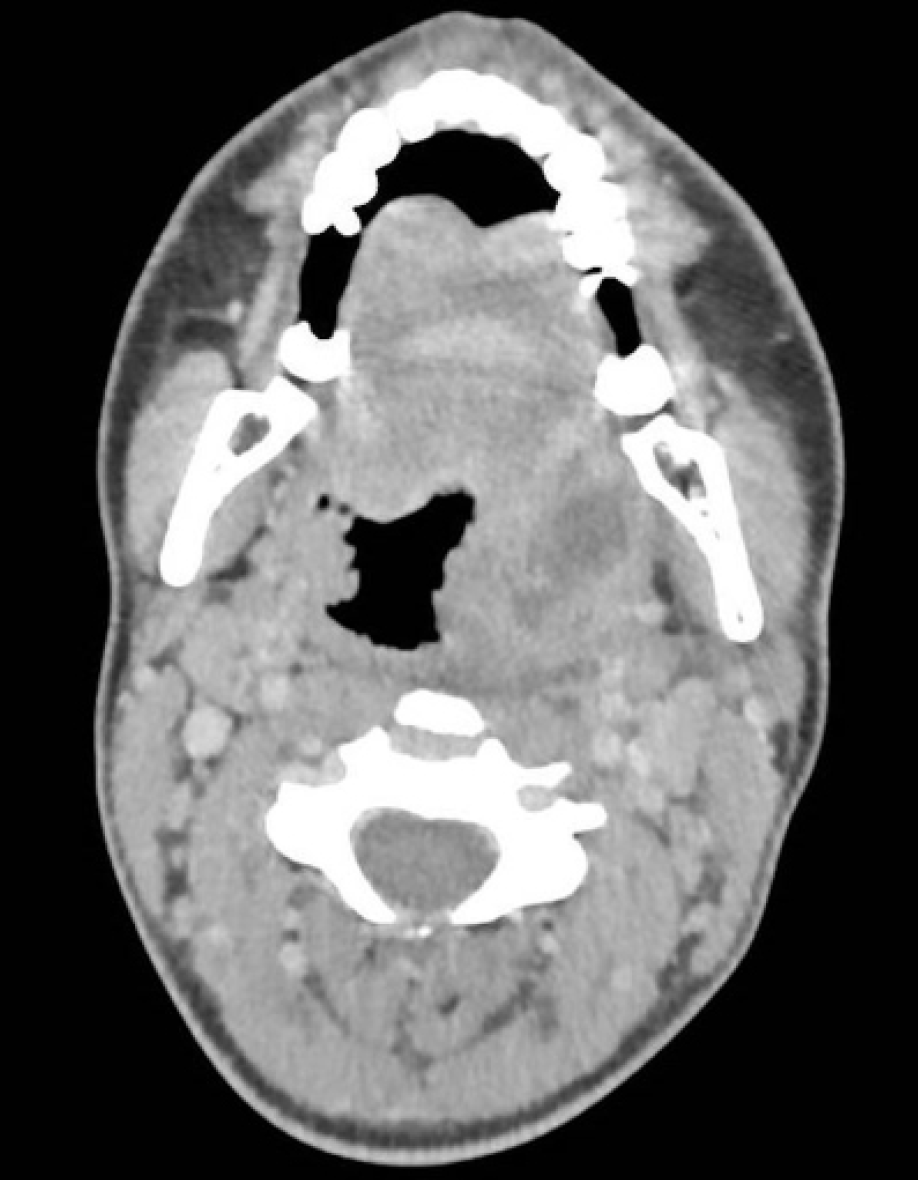

A 27-year-old previously healthy female was referred to our tertiary care center from a local clinic with a diagnosis of a left peritonsillar abscess confirmed by computed tomography (CT) (Figure 1). She reported a two-week history of odynophagia, which had started two weeks after a sexual encounter. Her symptoms have worsened over the last three days, with the onset of a dysphonia and trismus.